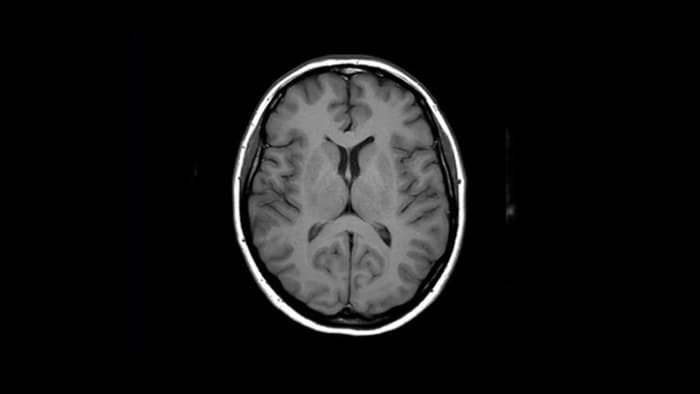

Pewność diagnostyki Zapewnia do 60% wyższą rozdzielczość przestrzenną przy takim samym czasie skanowania.4

Magnes Ingenia Ambition 1.5 Tesli to technologia rezonansu magnetycznego następnej generacji. Łączy w sobie najważniejsze aspekty skutecznego systemu rezonansu magnetycznego.